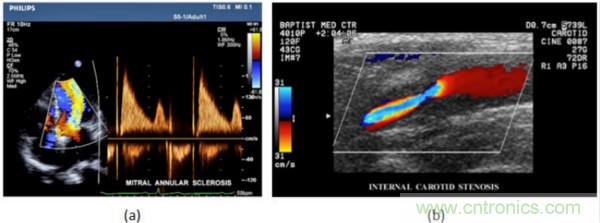

在CW和PW多普勒模式中,流信息是從一個(gè)聚焦聲束中獲得的,類似于A模式成像。在20世紀(jì)80年代,研究人員基于彩色多普勒技術(shù)完成了血流分布的二維信息可視化。彩色多普勒處理也是基于B模式/PW模式信號(hào)路徑。從感興趣區(qū)域收集多幀RF數(shù)據(jù)。由于感興趣區(qū)域中的血液流動(dòng)導(dǎo)致圖像幀之間存在數(shù)據(jù)差異。相域中的自相關(guān)和時(shí)域中的互相關(guān)兩種算法可從RF數(shù)據(jù)中提取數(shù)據(jù)方差(即血流速度和方向信息):。根據(jù)預(yù)定義的顏色漸變條相應(yīng)地映射包括速度和方向的血流信息。通常,藍(lán)色和紅色代碼分別識(shí)別朝向和遠(yuǎn)離換能器移動(dòng)的血流。當(dāng)流速增加時(shí)使用更亮的顏色,反之亦然。顏色映射的2D分布始終疊加在B模式圖像上,以實(shí)時(shí)同時(shí)顯示個(gè)體解剖結(jié)構(gòu)和血流。它對于診斷心血管疾病,如血管閉塞和心臟瓣膜反流,極其有用。典型的彩色多普勒圖像如下圖所示,(b)顯示頸動(dòng)脈狹窄引起的血流流速變化。

圖7.彩色多普勒成像:(a)以彩色多普勒和CW模式獲得的圖像(由Philips提供); (b)顯示頸動(dòng)脈狹窄的彩色多普勒(由GE提供)